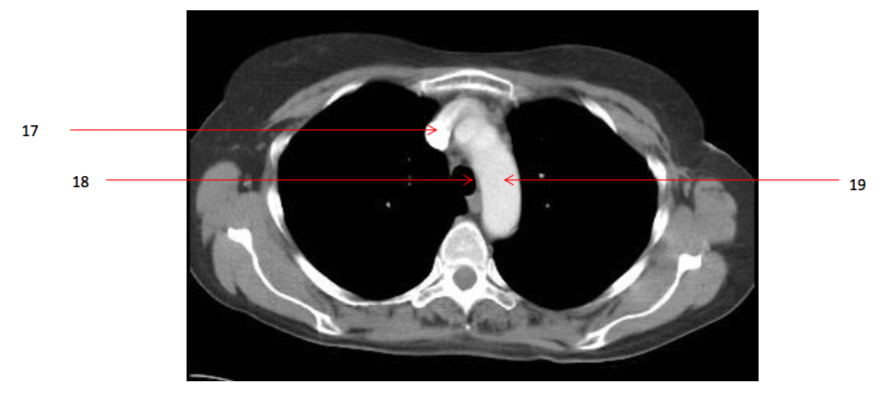

16

Number 17?

A

18

Number 20?

19

Number 18?